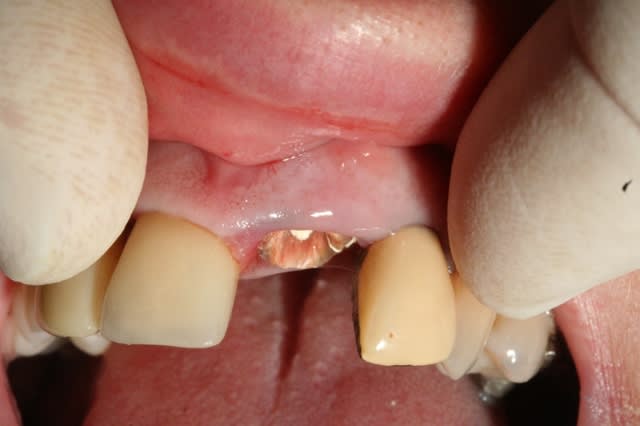

voilà à quoi ça ressemble aujourd'hui...

!! Quelle est l'étiologie de cette lésion ?

Le patient a t-il "bénéficié" d'un traitement ortho ?

Tu veux vraiment garder ça ?

il y a un trauma occlusal, à l'évidence. mais le trauma n'est qu'un facteur aggravant.

la patiente est en traitement paro en attendant une réévaluation dans trois à quatre mois.. mais elle est ouverte à tout.

n'importe qui d'autre t'aurait adressé cette radio,tu aurais répondu extraction,implant,que passa?